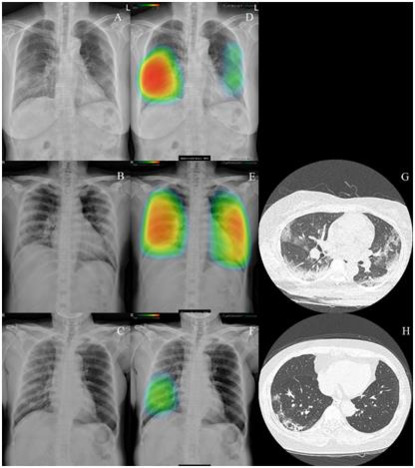

루닛은 유럽에서 흉부 엑스레이 영상 진단 보조 시스템인 '루닛 인사이트 CXR'과 유방암 진단 보조 시스템 '루닛 인사이트 MMG'에 대해 유럽 CE 인증을 획득했으며, 유럽 법인과 미국 법인도 설립해 시장 공략을 강화하고 있다. 루닛은 현재 미국 FDA 인허가를 추진 중이며, 올해 상반기 승인을 받을 것으로 기대하고 있다.

루닛 인사이트 CXR로 코로나19 폐렴이 표시되는 흉부 엑스레이 이미지. /루닛